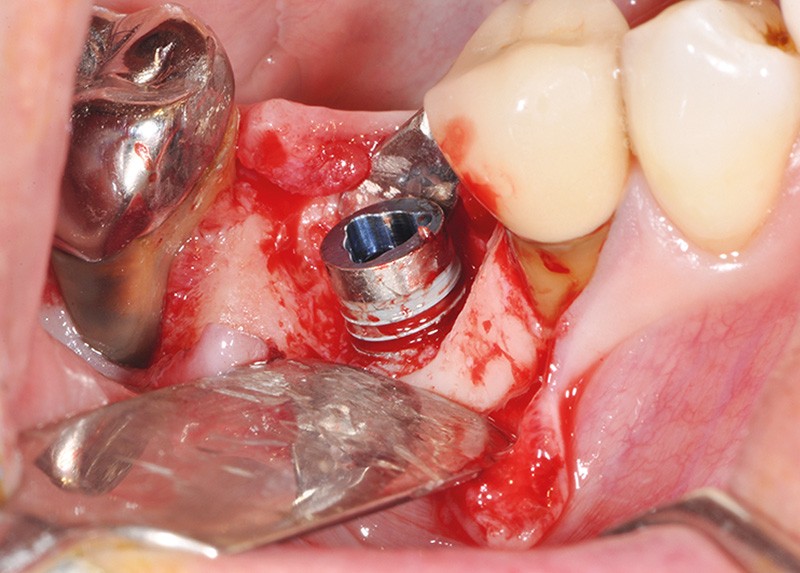

La stabilité des tissus mous autour des implants apparaît également comme un facteur très déterminant. L’absence de barrière kératinisée stable crée une mobilisation haute des tissus jusqu’au col implantaire. Cela a pour conséquence l’apparition de déhiscence gingivale, puis la disparition de l’os vestibulaire ou lingual.

La surface implantaire, ainsi exposée, fait office de porte d’entrée bactérienne. L’état de surface et sa capacité à fixer plus ou moins facilement les bactéries jouent alors un rôle primordial dans l’évolution de la pathologie.

Ce sujet est depuis de nombreuses années discuté et étudié dans le monde de l’implantologie. Il est évident que certaines surfaces présentent, soit par leur mode d’obtention, soit par leur niveau de rugosité, davantage de risques.